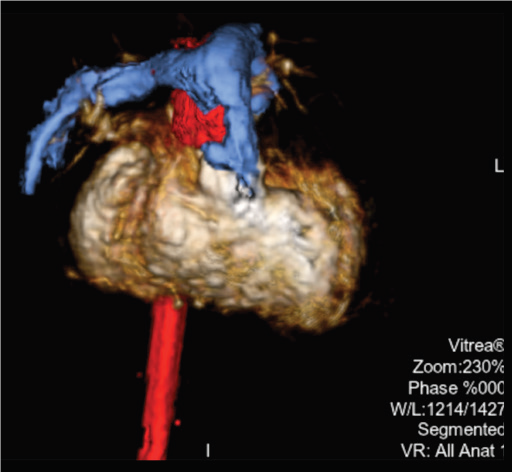

Програмне забезпечення MM Roadmap (або Multi-modality fusion) забезпечує додаткову інформацію завдяки 3D-візуалізації судинної анатомії, що успішно використовується при плануванні та навігації транскатетерної заміни клапану для лікування вроджених вад серця.

MM Roadmap дозволяє суміщувати 2D-флюороскопічні зображення з раніше отриманим 3D-об’ємом. Це може бути КТ або МРТ об’єм при чому незалежно від виробника сканера, або з ангіографічної системи Canon.

Суміщене зображення на моніторі змінюватиметься синхронно в залежності від нахилу С-арки, зміни SID, поля огляду, висоти та положення деки столу.

Можливість використання програмного забезпечення MM Roadmap під час складних втручань допомогає скоротити тривалість опромінення та об’єм введеної контрастної речовини..

Завдяки маркерам співставляють МРТ об’єм зі скопічним зображенням.

Для точного співставлення використовують рентген зображення в прямій та боковій проекціях.

3D анатомія використовується як дорожня карта (так зв. Roadmap)

Накладений 3D об‘єм полегшує маніпуляцію катетером через складну анатомію пацієнта, допомогає точно розташувати стент і клапан легеневої артерії.